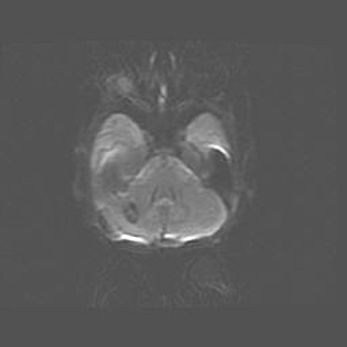

Церебральная ишемия II.

Возраст: 7 дней

Вес: 3350 г

Пол: женский

Окружность головы: 35 см

Срок гестации: 39 недель

Ишемия головного мозга – это состояние, которое развивается в ответ на кислородное голодание вследствие недостаточного мозгового кровообращения. У новорожденных она является следствием дефицита кислорода, что ведет к метаболическим расстройствам различной степени тяжести в тканях головного мозга, в том числе к развитию коагуляционных некрозов и гибели нейронов.